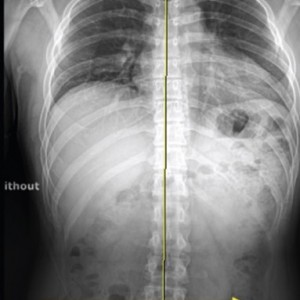

이제는 하세요!

엑스레이 검사

CT 검사

MRI 검사

족압 분석 검사

모아레 근육 균형 검사

적외선 체열 검사

다리 길이 검사

체성분 검사